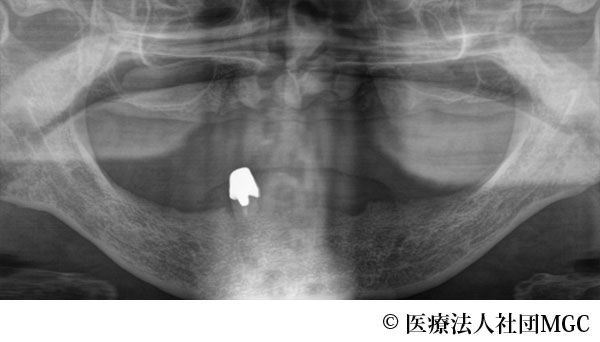

【症例3】上下All-on-4(オールオンフォー)

- 治療前

- 治療名

- 上下All-on-4(オールオンフォー)

- 費用

- 5,888,300円(税込)

- 期間

- 6ヵ月

治療内容

患者様の症状

上のブリッジが取れたことをきっかけに、全体に歯をきれいにしたいとご来院されました。

治療法

ご相談の結果、患者様の生活の質(QOL)を向上させ、しっかり噛め、審美的にも重視した、上下All-on-4(オールオンフォー)を行いました。

治療結果

機能性、審美性ともに改善し、満足していただけました。

※治療結果は患者様によって個人差があります。

治療を行う上での注意点(リスク・副作用)

インプラント周囲炎の可能性、まれに歯が欠ける可能性があります。